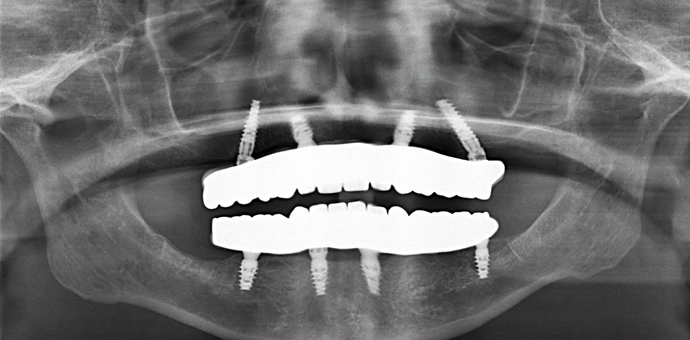

This retired professional had really healthy teeth until she was placed on several medications which caused dry mouth and quickly deteriorated her teeth beyond repair. She was extremely dissatisfied with her smile and wanted the best possible result. She had been offered snap on implant dentures by multiple dentists but she disliked the idea of removing her teeth at night and was therefore treated with full arch fixed bridges supported by implants all done in one day!

Procedures : extractions, implants, All on 4 , Teeth in a day, no bone grafting and full mouth reconstruction with monolithic zirconia bridges.